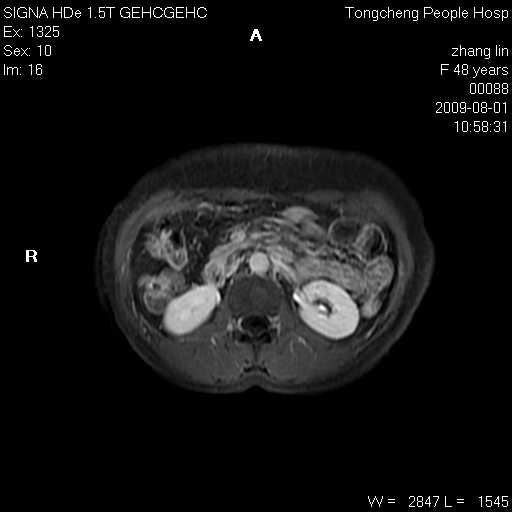

女,48岁。健康体检,彩超发现右肾占位性病变。平素健康。

临床诊断:右肾占位性病变,性质待定(囊肿?肿瘤?)。

上中腹部mr平扫+增强扫描,图像如下:

右肾上极见一类圆形病灶,t1wi呈等信号t2wi呈等高混杂信号,三期增强无强化,边界清---考虑囊肿出血。

同反相位均表现为等信号,病变无强化,考虑含蛋白的囊肿可能,弥散加权相或许有些帮助,

慢性胆囊炎